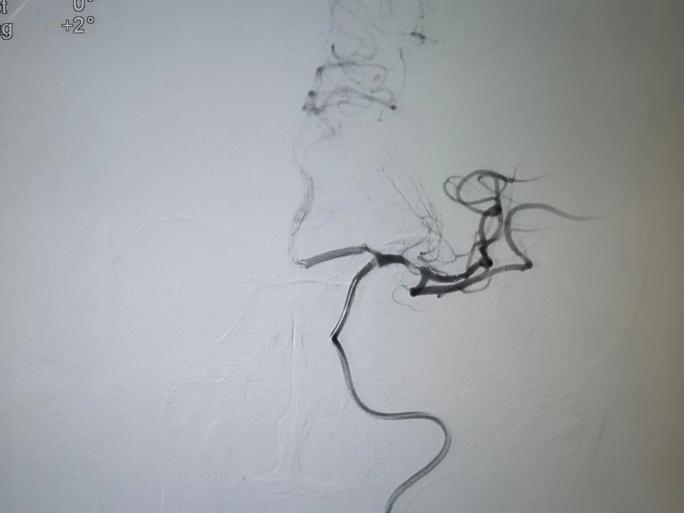

造影左側(cè)大腦中動(dòng)脈未顯

取栓后M1段局部重度狹窄,血流速度減慢

球囊擴(kuò)張治療后腦中動(dòng)脈M1

及以遠(yuǎn)段分支血流較前改善